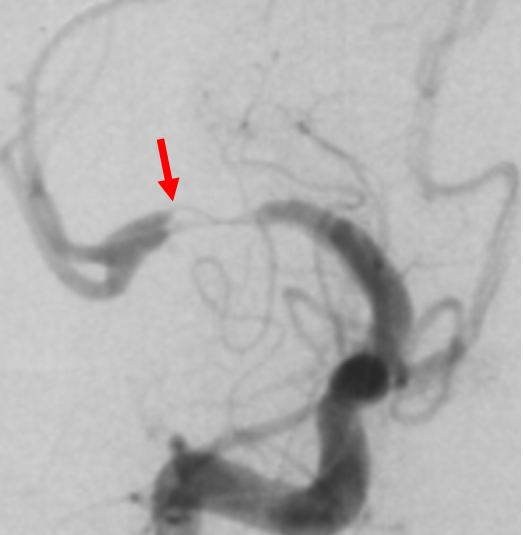

在放大的血管造影上看,可见外侧豆纹动脉在远端紧邻狭窄部位发出

由于担心球囊扩张后的雪犁效应,影响豆纹动脉的通畅性,选择比较保守的gateway球囊 2.75*15进行扩张

DSA复查(2019-10-31)提示严重支架内狭窄,豆纹动脉及早期颞支动脉依然保持通畅